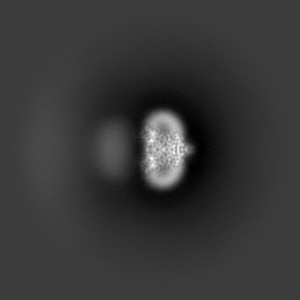

Cryo-EM structure of human Anion Exchanger 1 bound to Dipyridamole

Single-particle3.13 Å

Sample: Dimeric anion exchanger 1 (SLC4A1)